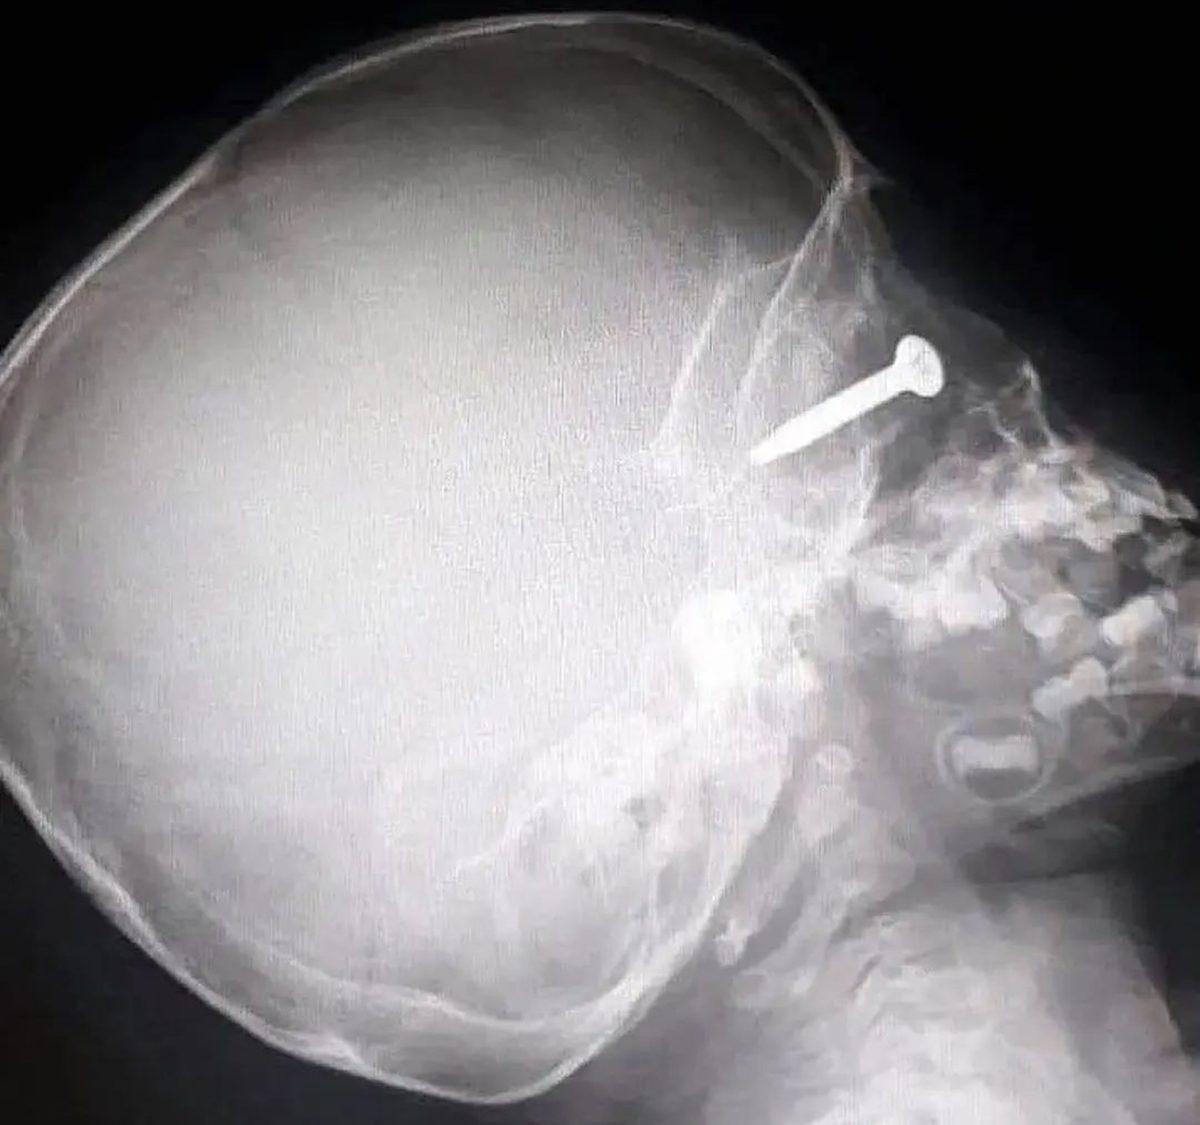

- Pakistan'da yaşayan bu kadının kafasına 5 cm'lik çivi girmesi her ne kadar ilginç olsa da bunun yaşanma sebebi çok daha ilginç.

3 kızı olan bu kadın, kocasının erkek çocuk istemesi üzerine hocaya gidiyor ve bu hoca, bebeğin erkek olması için kadının kafasına çivi çakıyor!